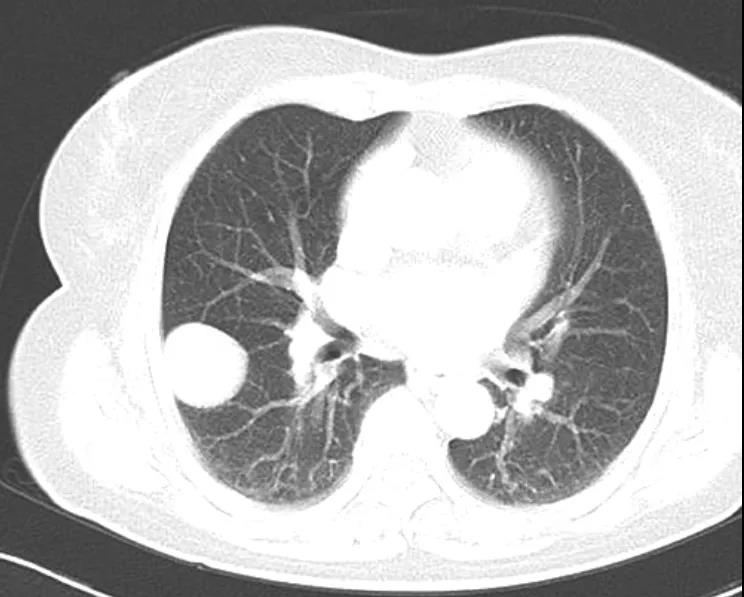

肺错构瘤

钙化影(尤其特征性的「爆米花样」钙化)和脂肪影是错构瘤最重要的影像学特征。肺错构瘤钙化发生率为 25-30%。CT 增强病灶大多无强化或轻度强化。

需注意:1. 瘤体较小、扫描层厚不够薄,较小钙化和脂肪影容易漏诊。2. 错构瘤一般无胸膜牵拉征、毛刺,但凡事无绝对!